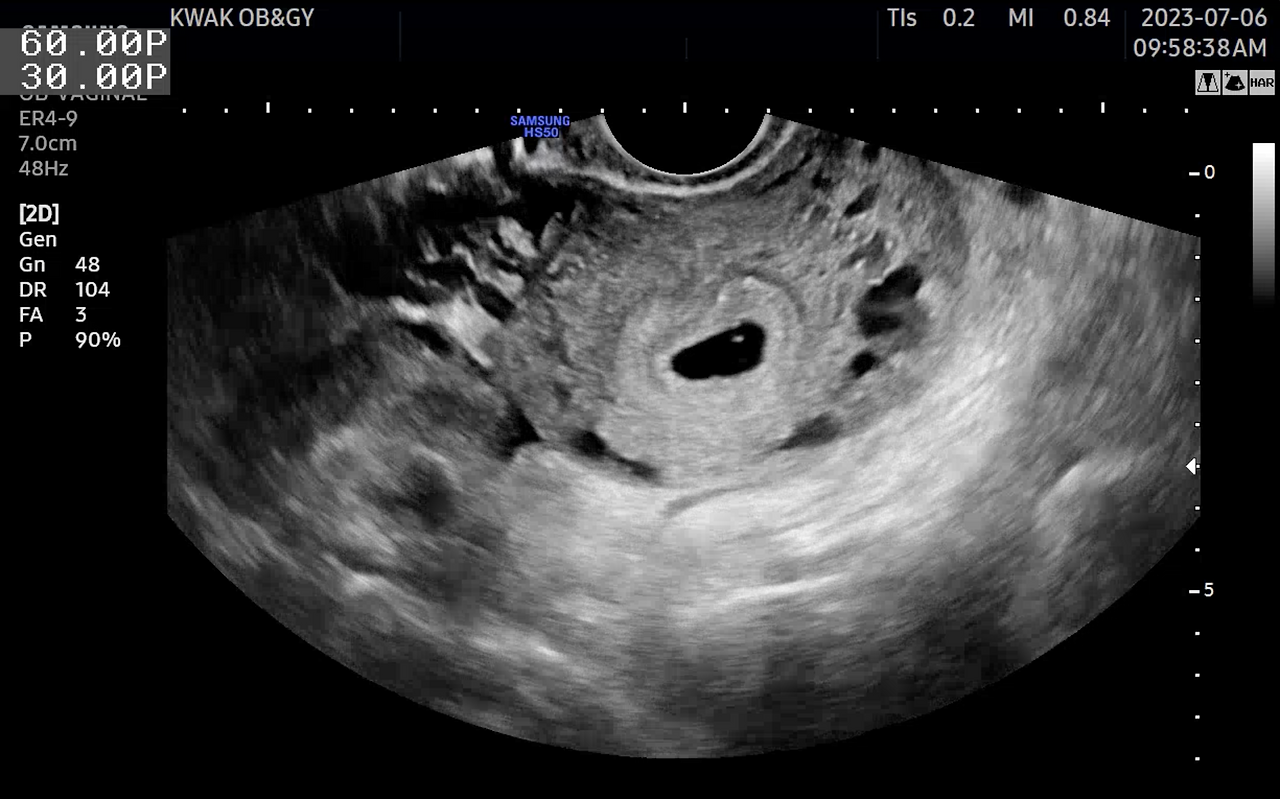

우리에게 찾아온 아이를 처음 만나러 갔던 병원에서 나는 또 다른 우주를 만나게 되었고 나의 'Pale blue dot'을 보았다.

희미하게 보이는 작은 생명에서 심장이 뛰고 우리보다 조금 바쁘게 움직여 자신만의 세상을 갖추어 간다.

수천 년의 시간을 통해 '인류'의 역사와 문명이 만들어진 것처럼, 10개월이라는 시간 동안 저 작은 점안의 생명은 '인체'를 만들며 스스로 놀라운 발전을 해간다.

아내의 뱃속 2mm도 채 안 되는 아이는 나에게 또 다른 우주가 되어 찾아왔다.

아이의 초음파 사진을 보고 칼세이건 박사의 책 속 Pale blue dot 사진이 떠 올라 만들게 된 노래가 하노의 Pale blue dot이다.